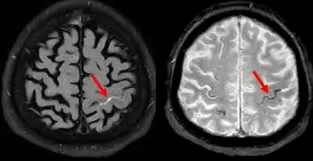

- એમઆરઆઈ: એમઆરઆઈ ચેપના ખૂબ જ વિગતવાર ચિત્રો પ્રદાન કરી શકે છે અને તે મગજ અથવા કરોડરજ્જુના ચેપને શોધવામાં મદદ કરી શકે છે.